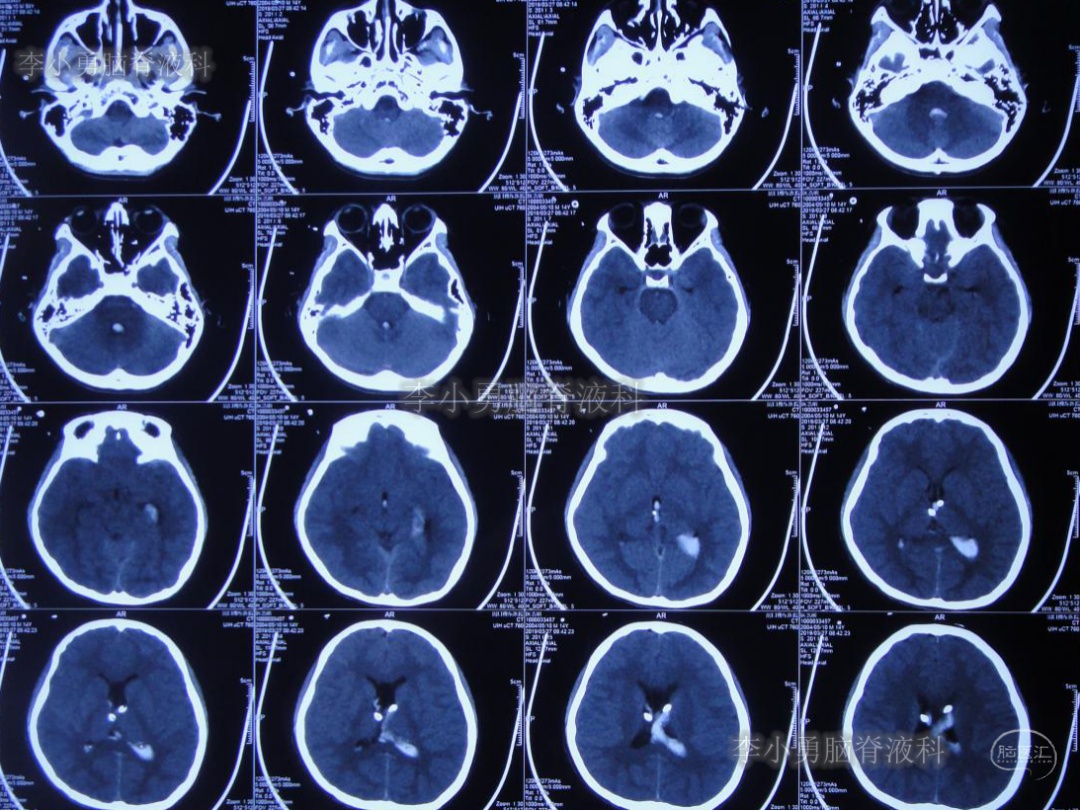

次日2019年4月3日(脑出血后8天),转至河南省郑州市某三甲医院;入院当日头颅CT(图-5)及CTA(图-6)检查结果:出血量较昨日无增加,动脉血管未见明显异常。

图-5:2019年4月3日头颅CT:出血量无增加

图-6:2019年4月3日头颅CTA:未见明显异常

继续给予脑室外引流1周后即2019年4月11日,再次复查头颅CT(图-7):脑室内积血明显减少,脑室不大。

图-7:2019年4月11日头颅CT:脑室内积血明显减少

复查完头颅CT后当天再次“常规”给予拔除脑室外引流管。此后每日行腰椎穿刺释放脑室内残留血性脑脊液。

为明确脑室内出血原因,拔除脑室外引流管1周后即2019年4月18日,行脑血管造影(片子遗失)检查:左侧“脑室内动脉瘤”。

为防止动脉瘤破裂,停止了每日的腰椎穿刺治疗,并积极完善动脉瘤夹闭术前准备。拔除第二次脑室外引流管后12天即2019年4月23日,患者出现哭闹、呕吐、发热及烦躁症状,紧急检查头颅CT(图-8):脑室较前略扩大,未见明显积血。

图-8:2019年4月23日头颅CT:脑室略扩大